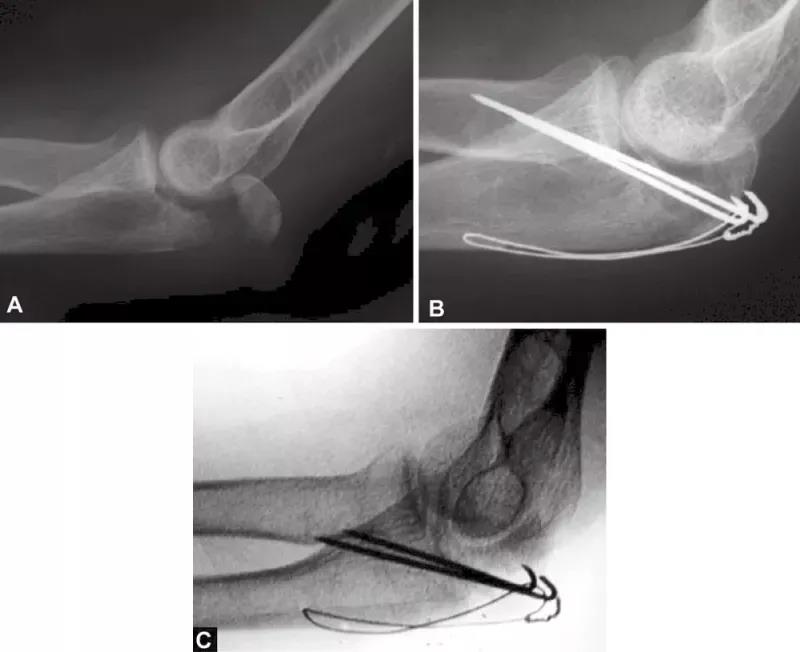

当存在鹰嘴关节面部分压缩时,必须将其对应肱骨滑车抬高复位。在三头肌止点用钢丝牵开鹰嘴尖端(图4),复位压缩骨折,用细克氏针将其推靠在肱骨滑车上维持位置。克氏针必须紧贴压缩骨折部位的软骨下骨来维持位置。此时,用高质量的侧位X线片检查来确定压缩骨折的复位,克氏针的位置是否良好是非常必要的。另一种方法是采用松质骨植骨来支撑复位的压缩骨折。

图4A和B(1)将鹰嘴拉下复位关节内松动的骨片,用横向箭头所示细克氏针,将其推挤在滑车上维持复位;(2)钢丝环穿过三头肌止点周围将鹰嘴拉下;(3)克氏针紧贴软骨下骨插入支撑松动的关节内骨片(给向箭头所示克氏针)